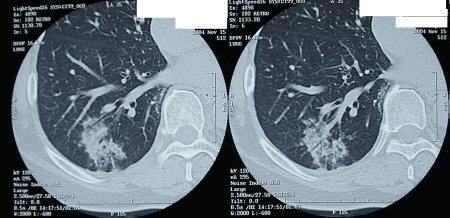

右 S10 の肺胞上皮癌。

無症状で 検診にて 発見。

無事に 下葉切除 終了し

術後診断にて Stage 1A

pT1N0M0 とされる。